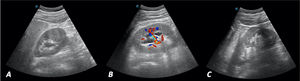

Ante el cuadro sugestivo de cólico renoureteral derecho, se decide realizar ecografía a pie de cama en consulta con los siguientes hallazgos: riñón derecho con dilatación de la vía excretora sugerente de hidronefrosis grado II/IV (figs. 1A y B). Vejiga bien replecionada con imagen anecoica tubular en el corte longitudinal que corresponde al uréter distal dilatado (fig. 2A). En el interior de la vejiga se observa imagen anecoica con borde hiperecoico bien definido que sugiere ureterocele y en su interior, una imagen hiperecoica con sombra acústica posterior de 9,76mm compatible con litiasis (fig. 2B). Riñón izquierdo (fig. 1C), hígado, vesícula y vía biliar intra y extrahepática, bazo, zona pancreática y próstata sin alteraciones.

A) Corte longitudinal. Imagen anecoica a la entrada de la vejiga, que corresponde al uréter dilatado. B) Corte longitudinal. Vejiga bien replecionada con imagen anecoica, con borde hiperecoico bien definido (imagen quística) que sugiere ureterocele. En su interior imagen hiperecoica con sombra acústica posterior de 9,76mm compatible con litiasis.

La prueba diagnóstica de elección es la ecografía, donde podrá detectarse una imagen en la pared posterior de la vejiga delimitada por una línea hiperecogénica bien definida, redondeada, de pared fina, que cambia de tamaño durante la exploración en tiempo real, sin doppler en su interior. En ocasiones se puede visualizar el uréter dilatado en la zona posterior a la vejiga2,5, como el descrito en este caso. Los uréteres son estructuras de calibre muy estrecho no visibles en ecografía de forma habitual6, salvo en situaciones patológicas donde sufran gran dilatación, como se muestra en la figura 2A. La ecografía permite, además, valorar complicaciones derivadas del ureterocele, como la dilatación del tracto urinario (reflejo ureterovesical o hidronefrosis), permitiendo establecer el grado y gravedad de la afectación renal2,5. El estudio se puede completar con otras técnicas como cistografía, urografía intravenosa, gammagrafía renal, cistoscopia y tomografía axial computarizada (TAC), según cada caso4,5.